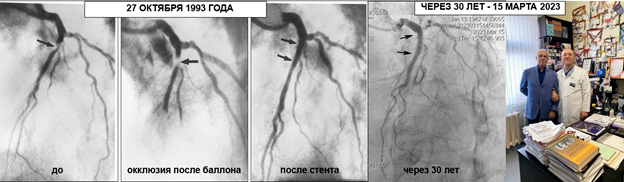

На днях нашу клинику ЦЭЛТ посетил пациент, которому 30 (!) лет назад нашим доктором Бабунашвили Автандилом Михайловичем была выполнена операция – имплантация стента в венечную артерию по поводу ишемической болезни сердца. Операция была выполнена 27 октября 1993 года и была первой в России операцией имплантации стента в венечной артерии сердца. На момент имплантации пациенту было 51, доктору 31. Первая имплантация стента типа Palmaz-Shatz диаметром 3.0мм была в несколько драматичной ситуации, поскольку был имплантирован по неотложным показаниям. Но… несмотря на это, до сих пор работает и подарил пациенту 30 лет счастливой жизни. Этот результат является мировым рекордсменом, поскольку в доступной мировой научно-медицинской литературе отсутствуют данные столь отдаленного успешного результата операции на венечных артериях сердца.